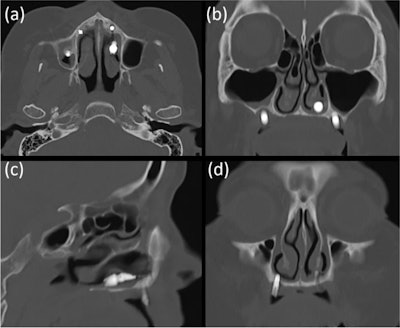

The CT image of the first patient shows that the implant was displaced in the left nasal cavity but not in the maxillary sinus (a-c). The implant of the right premolar area, which appeared to be placed in a spot with insufficient bone between the nasal cavity and the maxillary sinus on an x-ray, appears to penetrate the nasal floor.